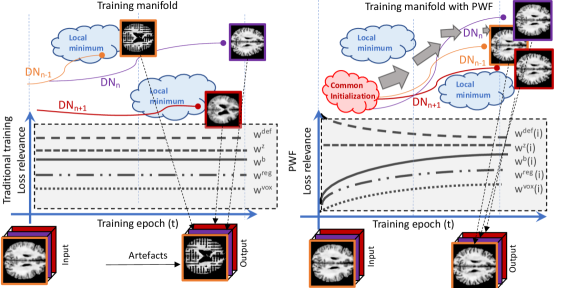

3.2.5 Profiling Weight Functions (PWFs) for 3D Training Consistency

In this section, we introduce PWFs that propose a way to dynamically weigh our five losses and unifying the training of the 2D slice-wise models [38] in a computationally efficient manner.

Due to the complexity and non-convexity of our total loss function, training each might be unstable. This is particularly problematic since convergence failures in a slice will generate spatial inconsistency artefacts in the synthetic 3D MRI. This is compounded by the adversarial components of DANI-Net ( and ), as GANs are known to be prone to training instability [43, 44].

The left block of Fig. 4 shows a hypothetical example that would create problems with classical adversarial training, as the competitor networks may reach a local minimum of the training manifold.

To overcome this type of instability, the PWFs will guide training. It is inspired by a multistage learning strategy where humans solve a complex visual problem, i.e., optimizing simpler sub-tasks first. Explicitly, PWFs guide the system to focus on fewer loss functions at a time, i.e., providing greater regularization. This is achieved by dynamically weighting each component loss during every training epoch . To do so, we use the following mean-reverting exponential function:

| (7) |

with parameters (, and ) optimized by a random search strategy on a grid, and measuring training convergence using the on a validation set. The right side of Fig. 4 depicts how PWFs help to avoid local minima and, in our case, ensure that different models avoid the spatial mismatch that can cause image artefacts.

The final step for maintaining 3D consistency between consecutive slices is to smooth slice-wise models using a Gaussian-weighted () average, that includes the nearest-neighbour slices.

Although traditional initialization techniques can be used within our pipeline (i.e. Xavier), we found better performance when all the models start from a common initialization (red cloud in Fig. 4). In practice, this common initialization consists of a model pre-trained with only 100 iterations on central axial slices of the training images.